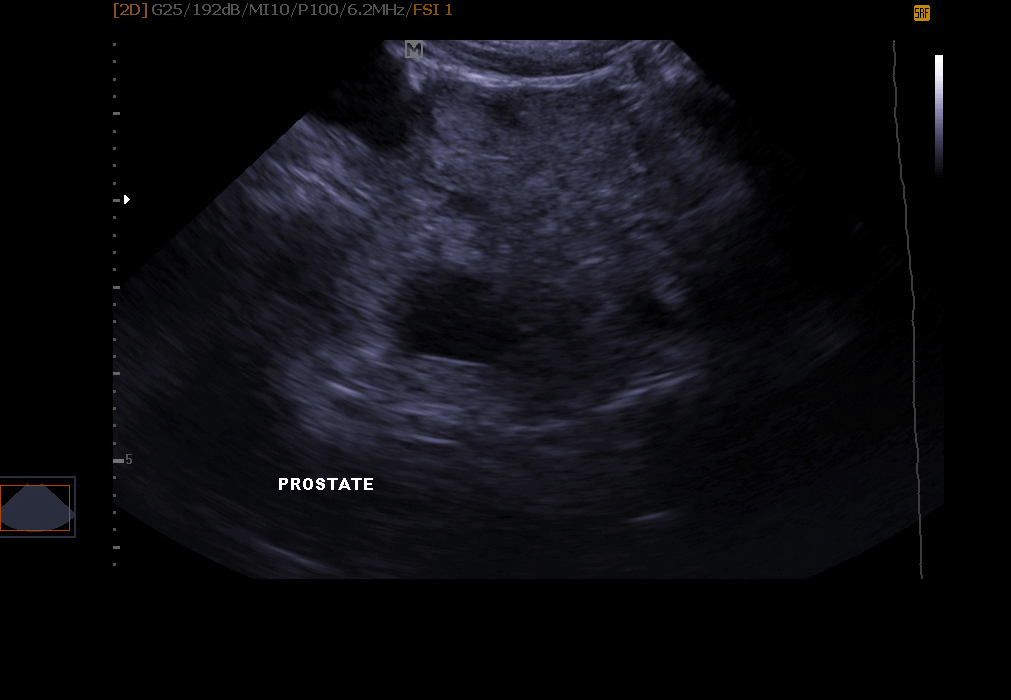

Examination of the genital system: infection of the uterus, gestation detectable from 18 to 21 days in the cat and the female dog, ovarian cysts, exploration of the prostate in the male.